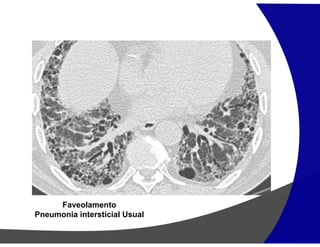

Fibrose Pulmonar

Achados por Imagem

• TCAR

Redução volumétrica

Opacidades reticulares subpleurais

Faveolamento (macro)

Bronquiectasias de tração

Gradiente de envolvimento apico-basal

Heterogenicidade espacial e temporal de distribuição

Faveolamento

Pneumonia intersticial Usual